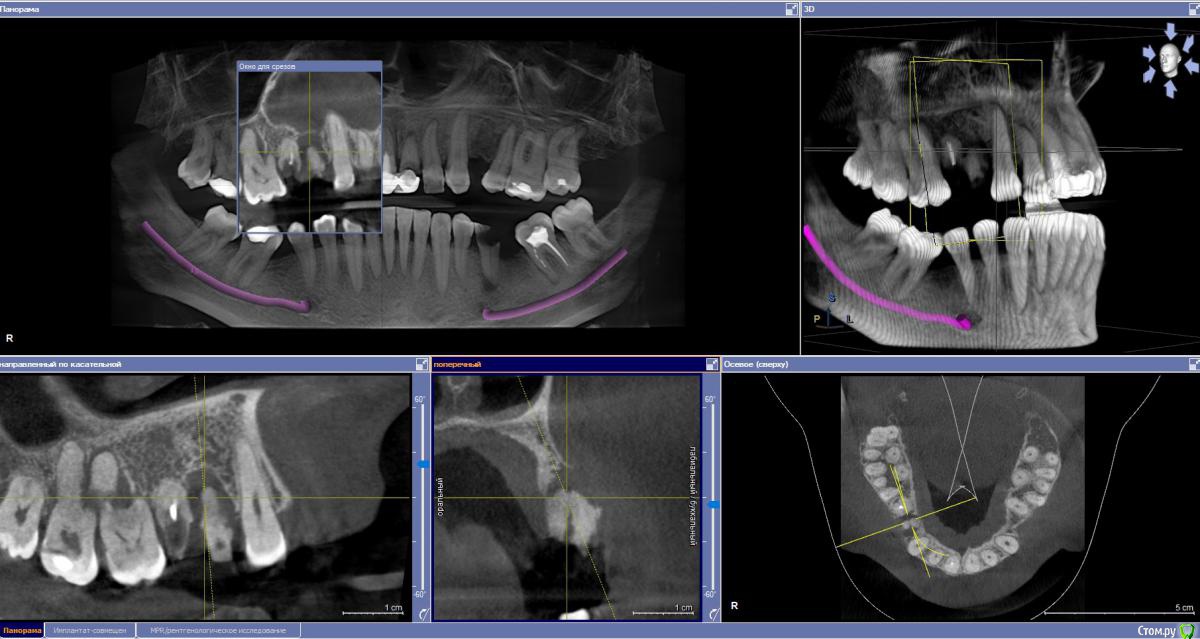

stomalolog Опубликовано 30 ноября, 2018 Поделиться Опубликовано 30 ноября, 2018 Добрый день. Пациенту назначили удаление корней 14,15. Вокруг 14 очаг резорбции, отсутствует вестибулярная стенка, на уровне шеек чуток кости.Собственно вопрос - что после удаления лучше сделать, для образования кости, сохранения десны ? Планируется мостовидный, но в любом случае уйдет десна, если ничего не сделать, не хочется получить яму. И пациент может созреть для имплантации.Какие варианты? A-prf и сверху сразу временные для формирования овоидов и поддержки, или графт-мембрана? Что лучше и может какие еще варианты ?Спасибо. Ссылка на комментарий